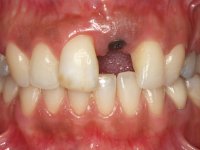

A paciente de sexo feminino de 28 anos de idade perdeu por traumatismo o incisivo central superior esquerdo. Preocupada com o seu sorriso, a paciente apareceu no consultório querendo alinhar os dentes antero-superiores para obter uma aparência mais natural. Sendo fumadora a paciente não apresentava problemas médicos dignos de registo.

A paciente apresenta um desvio da linha média superior de 6 mm para a esquerda. Resultado da ausência do incisivo central superior esquerdo, os dentes adjacentes inclinaram mesialmente para esta zona, limitando o espaço disponível para a reabilitação prostodontica. Existe uma significativa desarmonia dentária negativa no arco maxilar como resultado da ausência do 21, ausência do primeiro pre-molar com um espaço residual, significativa redução coronária do segundo pre-molar direito, migração dos dentes posteriores para os espaços não preenchidos e uma mesialização molar superior esquerda e direita com uma relação molar em Classe II. Ambos os caninos esquerdo e direito mostram uma relação Classe II na posição de inter-cuspidação máxima. A paciente apresenta uma linha de sorriso média, um biótipo gengival médio grosso, apresenta uma correcta higiene oral sem doença periodontal. Não apresenta hábitos para –funcionais. O exame radiográfico mostra uma significativa inclinação dos eixos dos dentes 11 e 22 com espaço entre a porção apical das raízes. A análise cefalométrica foi feita com o intuito de explorar a hipótese de conseguir arranjar espaço para a colocação de um implante e de uma coroa no local do dente 21. Finalmente a morfologia do osso residual presente na região anterior da maxila foi avaliado com uma TAC, revelando uma perda das dimensões da parede óssea vestibular.